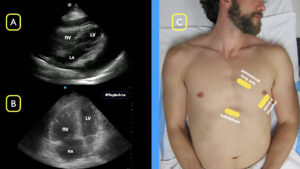

- Find the echo view before pause: During CPR, the clinician who is performing POCUS should attempt to find the ideal view of the heart. Often, this is a subxiphoid view, but can also be a parasternal long or apical four-chamber view (see Figure 1). The goal is to have a reasonable view before the CPR pause so that time is not wasted finding an adequate window.4

FIGURE 1: A) Subxiphoid view demonstrating a pericardial effusion with signs of echocardiographic tamponade B) Apical four-chamber (A4C) view demonstrating right ventricular strain in a patient with a massive pulmonary embolism C) Three views of the heart when attempting to find a good window to image during cardiac compressions. (Click to enlarge.)